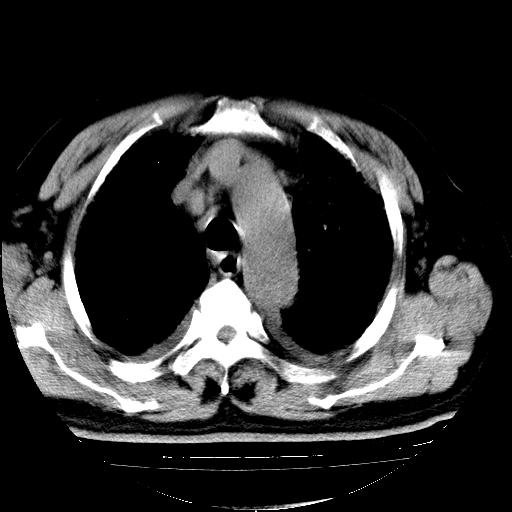

男,68岁,咳嗽、胸闷、发烧三天,查体:双肺散在湿罗音。

首先考虑特发型肺间质纤维化;两侧少量胸腔积液。

依据:1、两肺广泛条索状、网格状、蜂窝状改变。

双肺多发条索状、网格状及小灶状密度增高影。考虑慢支合并感染.间质纤维化,双侧少量胸腔积液

两肺广泛条索状、网格状、蜂窝状改变。肺间质纤维化,肺心病,双侧胸腔积液